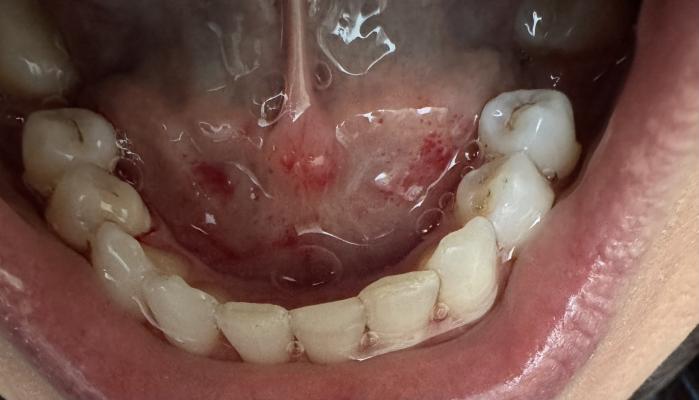

Фотографии пользователей: